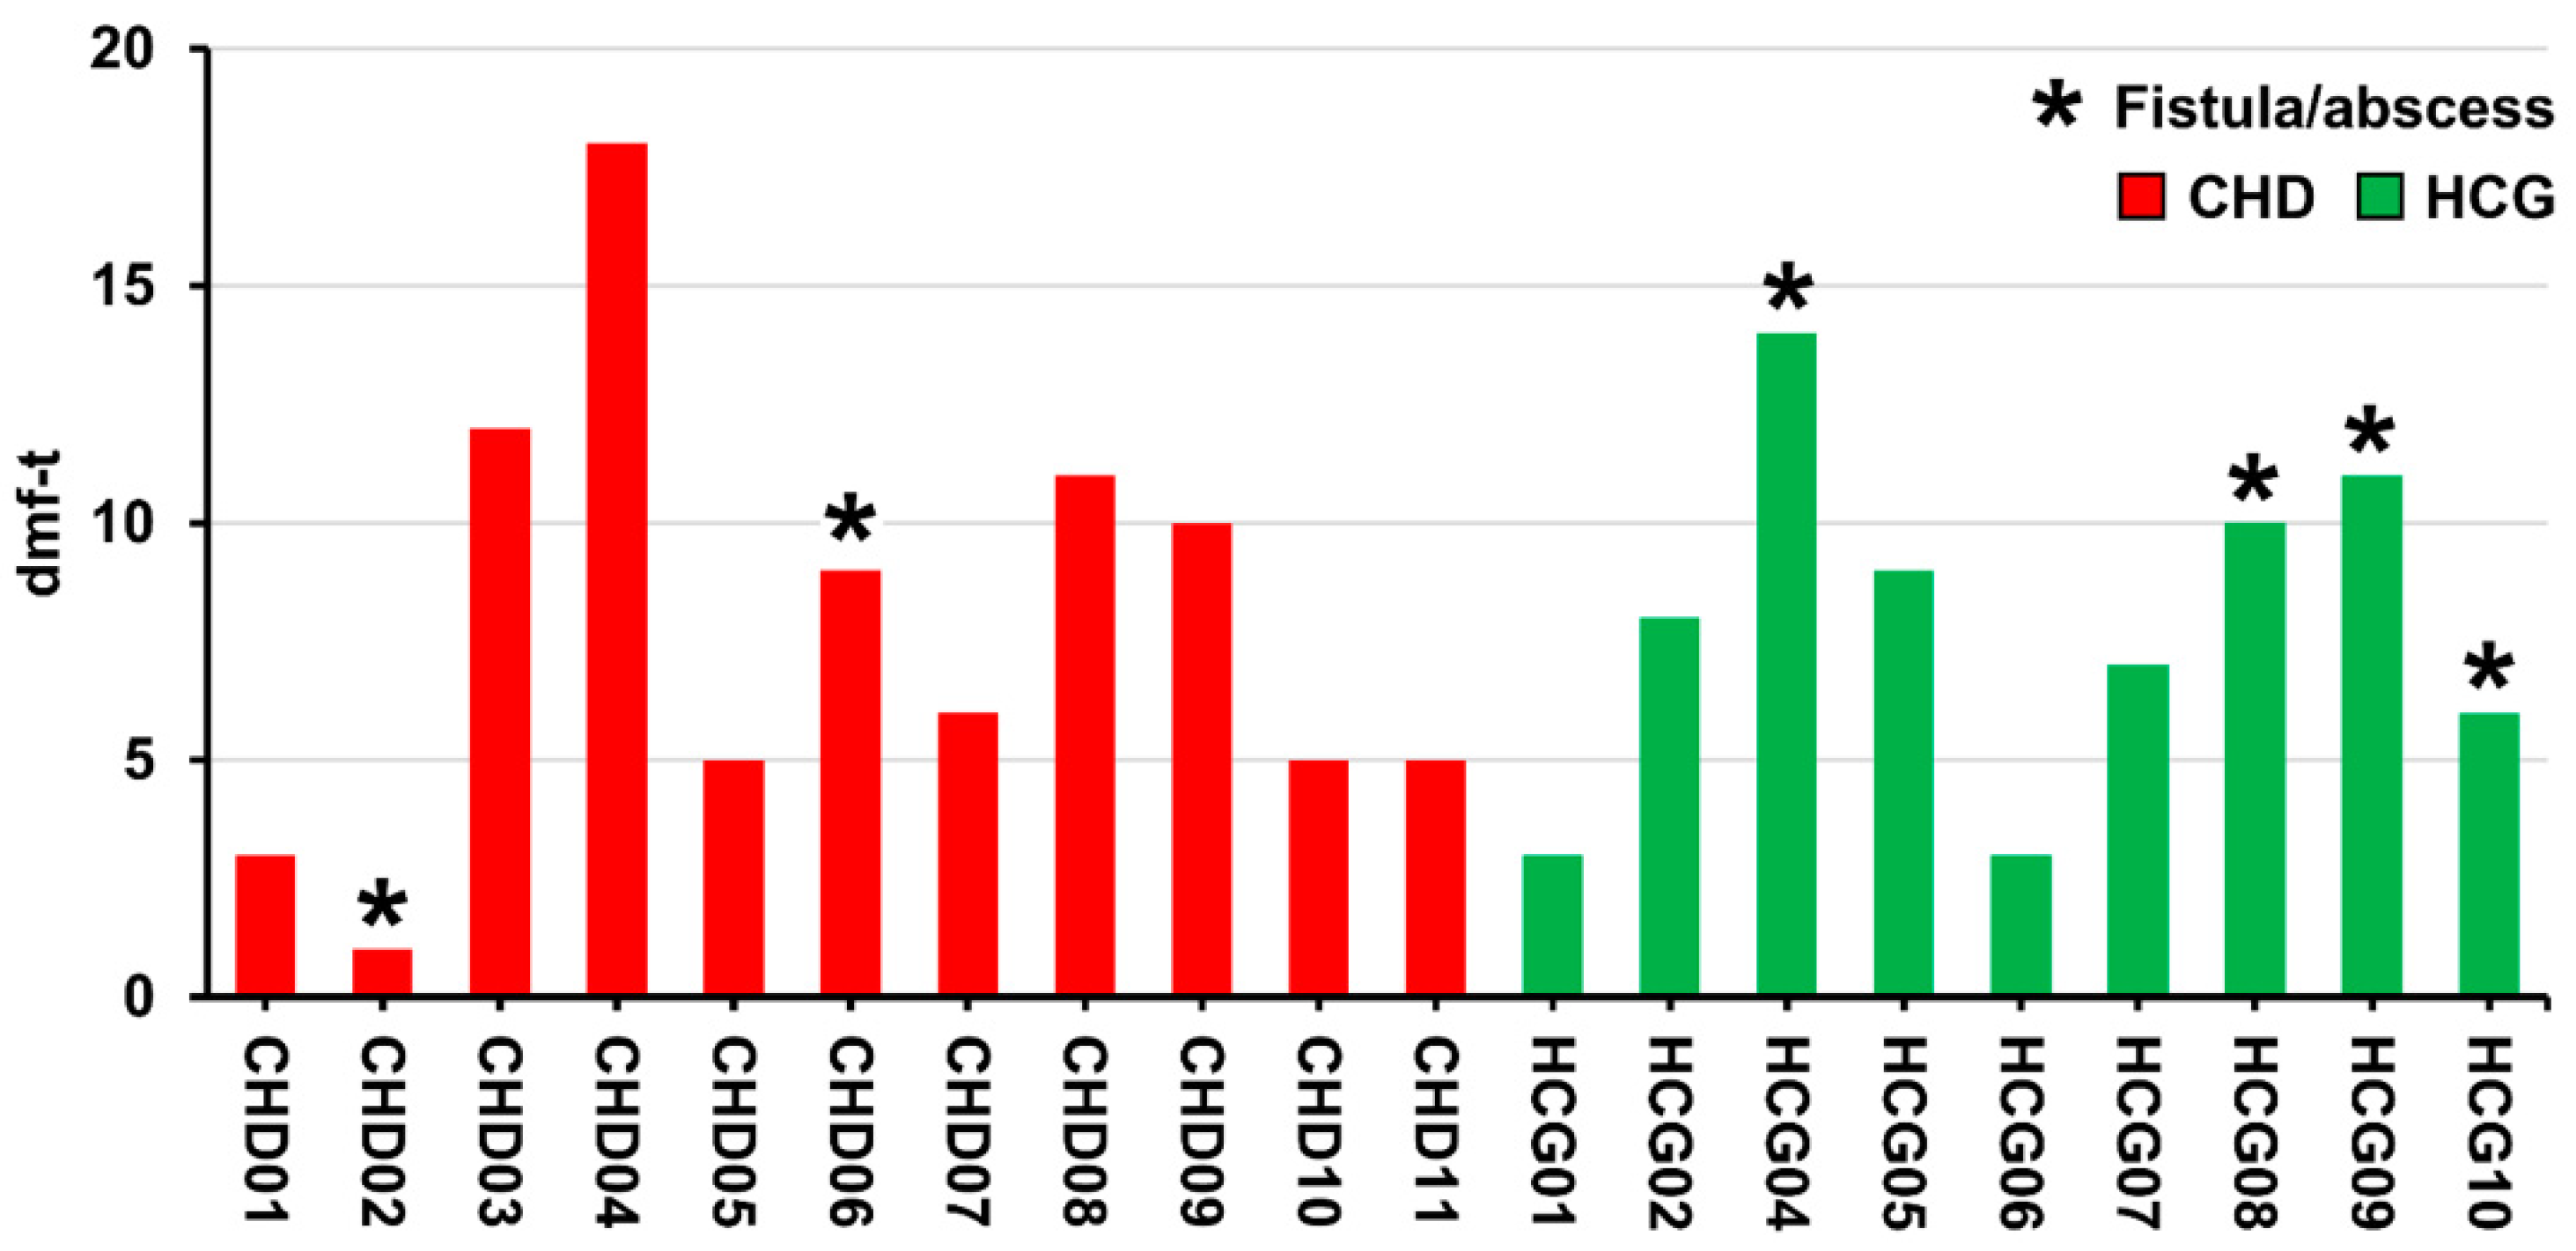

2.1. Dental Examination and Sampling